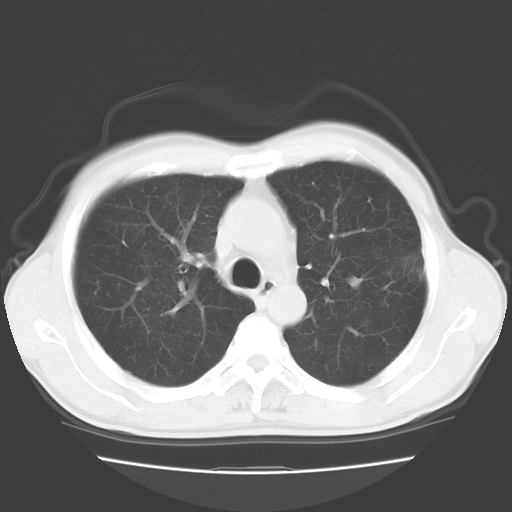

以下是引用随光逐影在2008-11-20 23:02:00的发言:[br]1)考虑左肺上叶周围型肺癌可能性大。2)两肺散在性肺泡积血。[br][br][本贴已被 随光逐影 于 2008-11-20 23:09:31 修改过]

以下是引用drzhang8888在2008-11-20 22:20:00的发言:[br]密集的短毛刺,血管集束,胸膜凹陷,周边型肺癌可能性大,另双肺多发磨玻璃影,考虑感染

以下是引用流浪星在2008-11-20 22:28:00的发言:[br]左肺上叶近外围区见一类圆形结节影,毛刺征、胸膜尾征阳性,临近肺组织见多发渗出灶。考虑1,炎症性病变。 2.周围性肺癌。建议抗炎治疗后复查。

以下是引用qc80012345在2008-11-21 5:53:00的发言:[br]支持;周围型肺癌诊断。增强扫描。